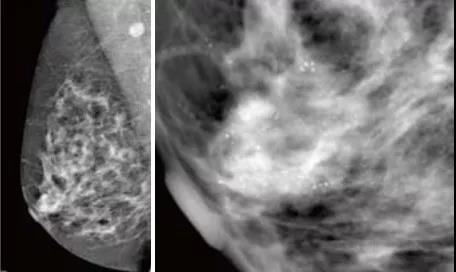

GE 平板數(shù)字乳腺機(jī)拍攝的右乳MLO,清晰顯示早期乳腺癌的沙粒樣鈣化,

此時(shí)乳腺觸診并沒有任何異常